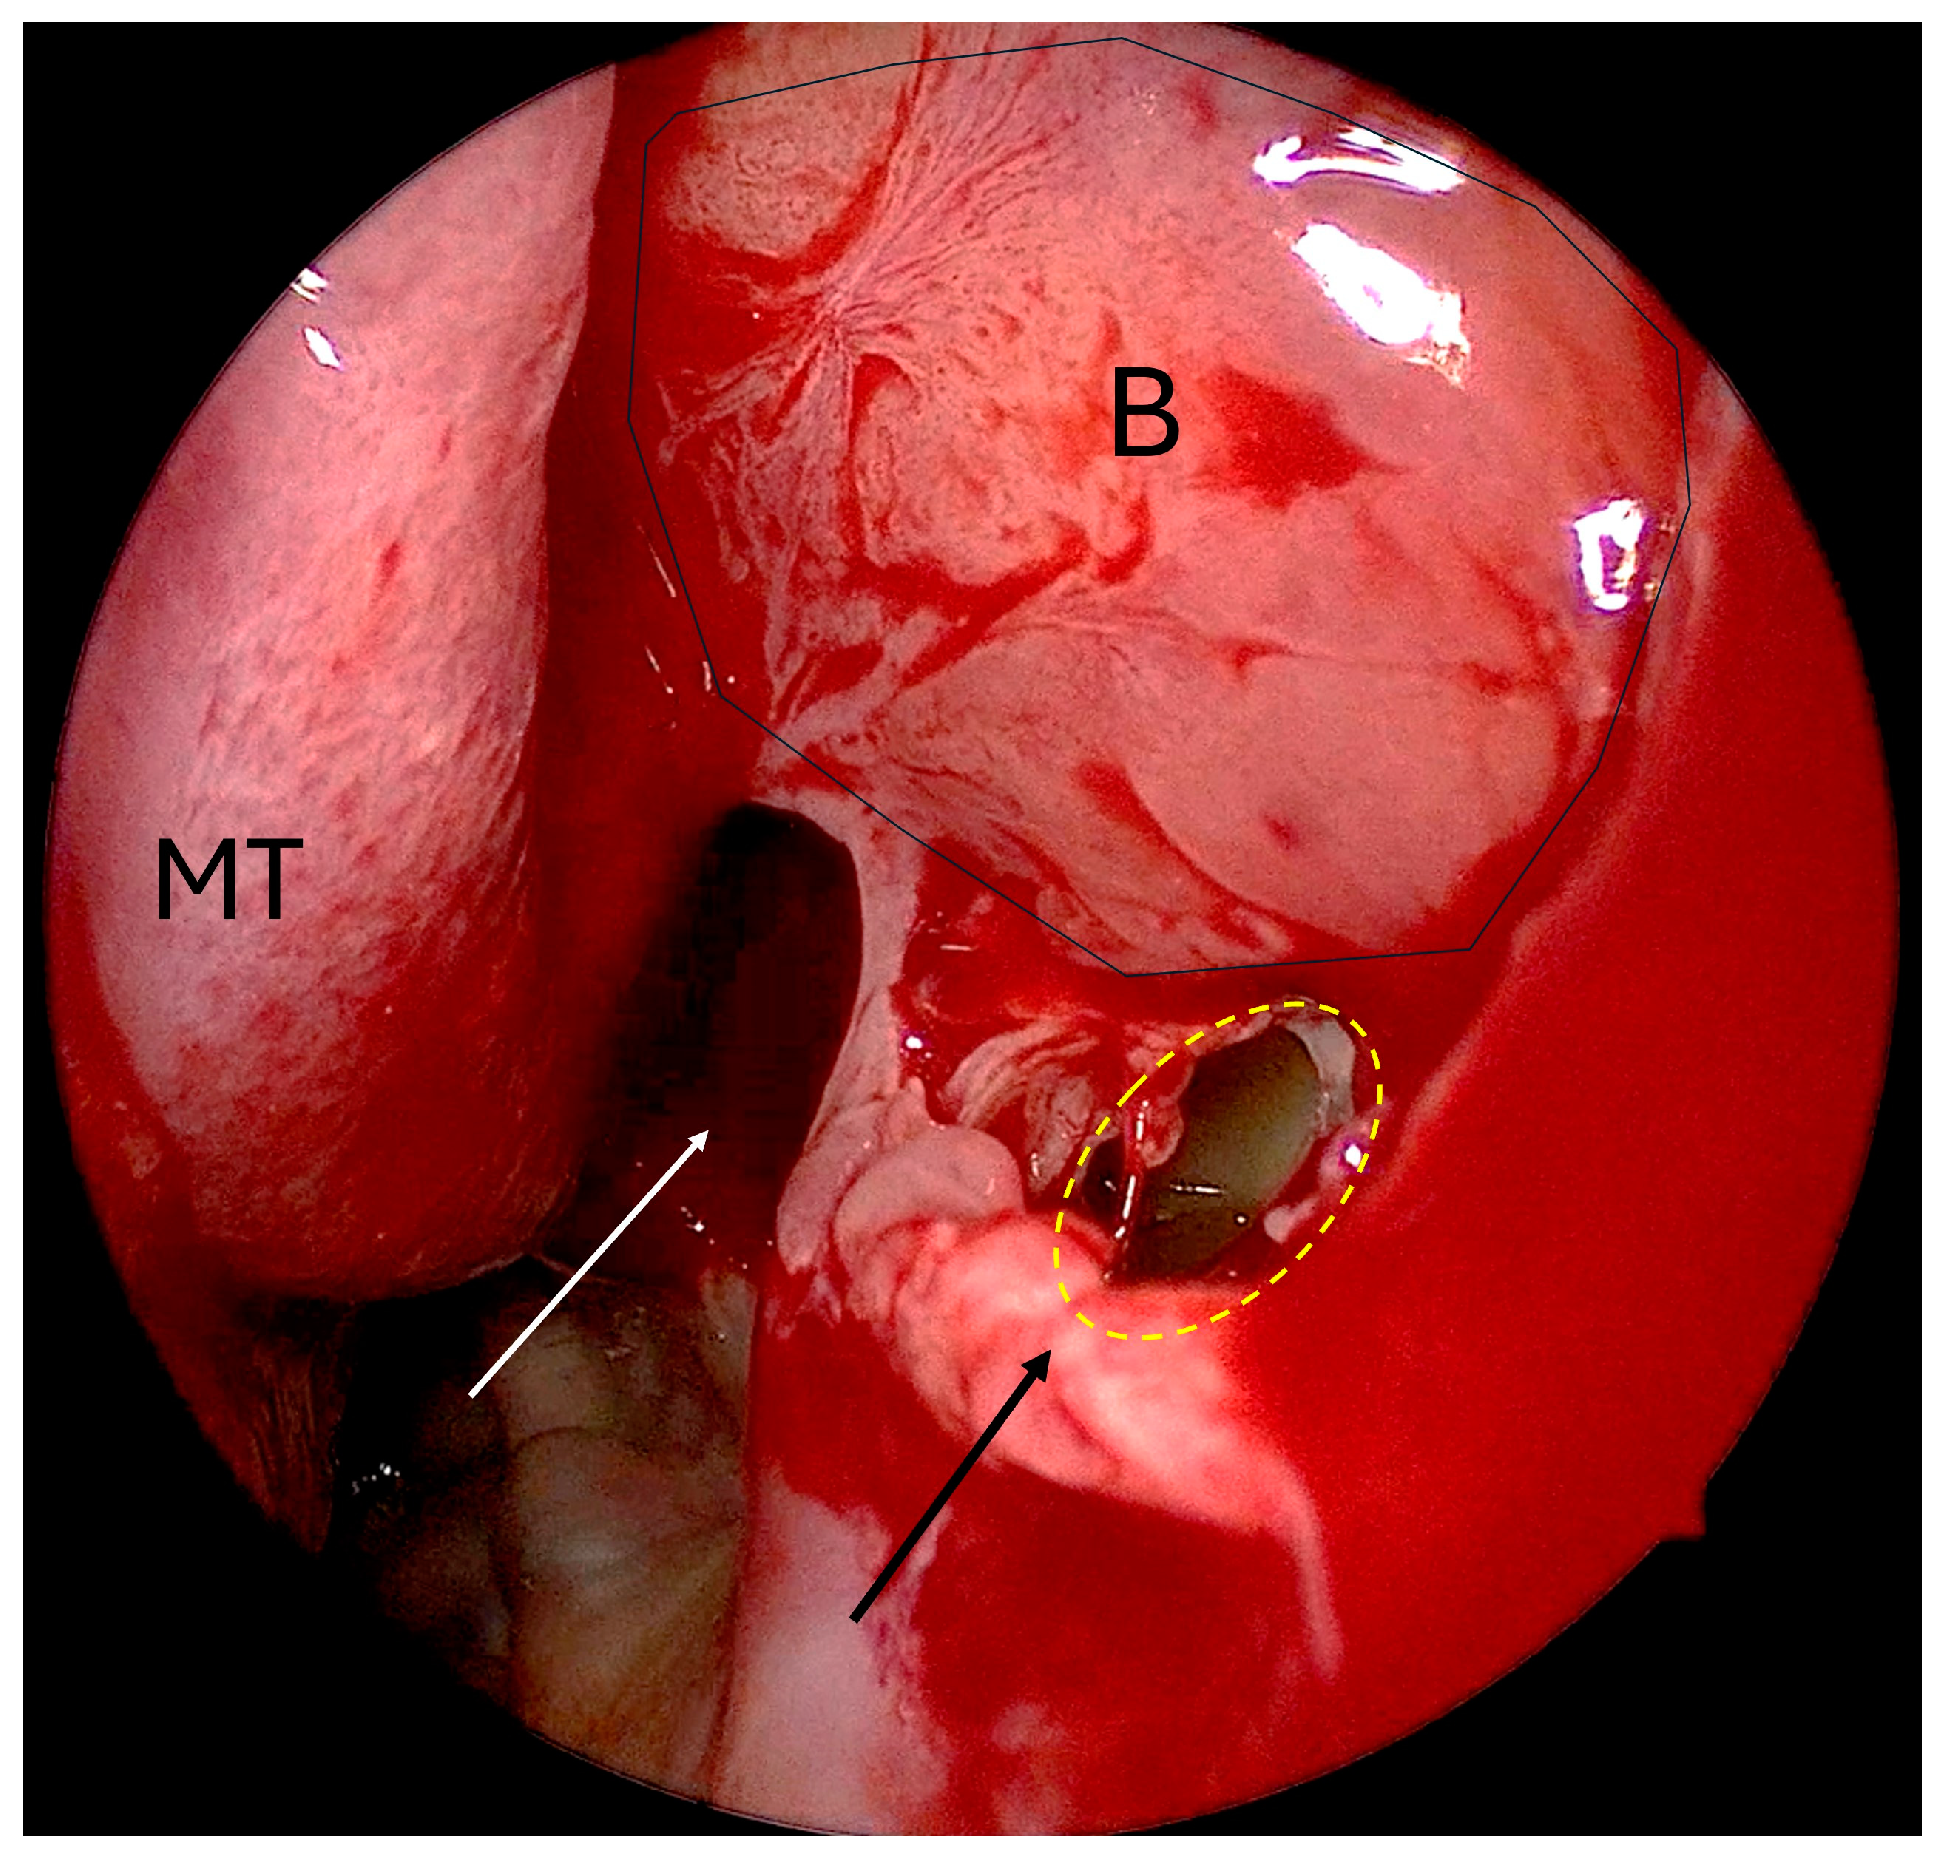

- Non-incorporated natural ostium/posteriorly placed maxillary antrostomy (Figure 2);

| Missed natural maxillary ostium in maxillary antrostomy | 27 (39.13%) | 23 (85.18%) |